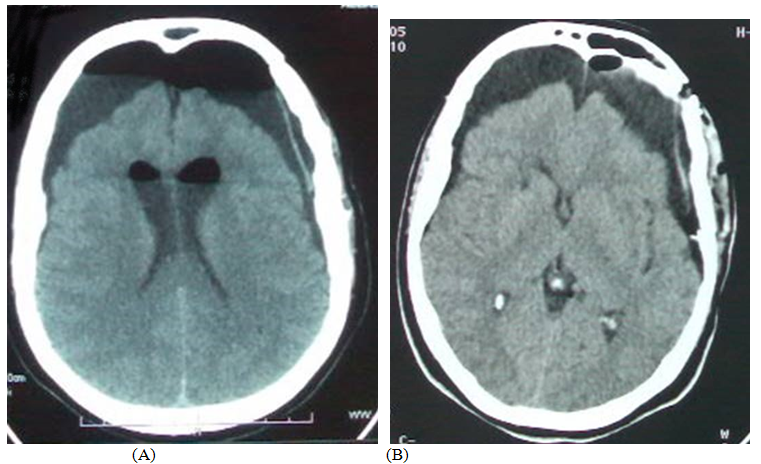

The cerebral MRI showed a sellar lesion inserted on the anterior clinoid process in hyposignal T1, hypersignal T2 with homogenous enhancement after gadolinium injection suggesting meningioma(Figure 1). Gross total removal “Simpson I” by left pterional approach was performed and the histopathological exam confirmed transitional meningioma. The post-operative course was marked by the anterior left and posterior rhinorrhea as well as meningitis, treated successfully by antibiotics with lumbar spinal drainage. However, 3 days later, the patient accidentally fell from her bed causing a CSF hyperdrainage bringing back more than 800CC, accusing excruciating headaches and disturbances of consciousness (GCS =12) without neurological deficit.

Figure 1 Cerebral MRI sagittal weighted T1 contrast (a), and coronal T2 showing anterior clinoid process meningioma with homogeneous enhancement (a) and hyperintense T2 (b).